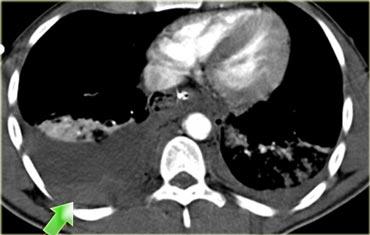

Trước tiên hãy quan sát các hình ảnh bên trái của bệnh nhân bị chấn thương gan.

Mô tả các dấu hiệu hình ảnh.

Sau đó tiếp tục.

Các dấu hiệu bao gồm:

- Mũi tên xanh lá: vùng giảm tỷ trọng hình bầu dục phù hợp với tụ máu

-

Mũi tên vàng: vùng giảm tỷ trọng hình tuyến tính phù hợp với đường rách.

Lưu ý rằng đường rách này đi qua nhánh trái của tĩnh mạch cửa - Mũi tên xanh dương: vùng giảm tỷ trọng mờ, ranh giới không rõ phù hợp với dập gan

- Dịch quanh gan

- Gần như có sự đứt ngang hoàn toàn của gan, nhưng cả hai thùy đều còn ngấm thuốc, cho thấy nguồn cung cấp mạch máu vẫn còn bình thường.